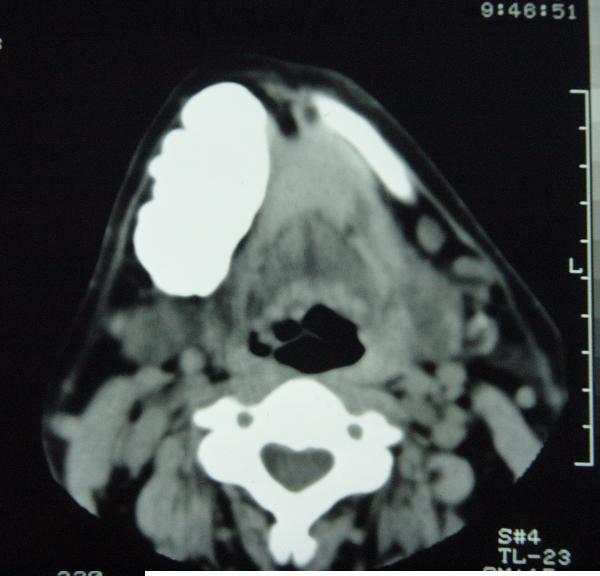

标题: CT12465:下颌骨肿瘤,请会诊 [打印本页]

标题: CT12465:下颌骨肿瘤,请会诊

发现下颌骨肿瘤近30年.逐渐增大.

考虑右侧下颌骨水平部及升部骨纤维异常增殖症可能性大。